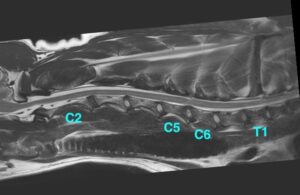

![[MR画像 矢状断像 T2強調画像]](https://saitovet.com/wp-content/uploads/2025/11/2-1-300x195.jpg)

第5および第6頚椎*の間における脊髄が上下から圧迫されている所見があり、明らかな椎間板の突出は認められない。

![[MR画像 背断像 T2強調画像]](https://saitovet.com/wp-content/uploads/2025/11/3-1-300x191.jpg)

![[MR画像 横断像(C5-6) T2強調画像]](https://saitovet.com/wp-content/uploads/2025/11/4-300x194.jpg)

この所見から脊椎の骨の増殖によって、脊髄が左右から圧迫される。

頚部脊椎脊髄症(ウォブラー症候群)と診断。